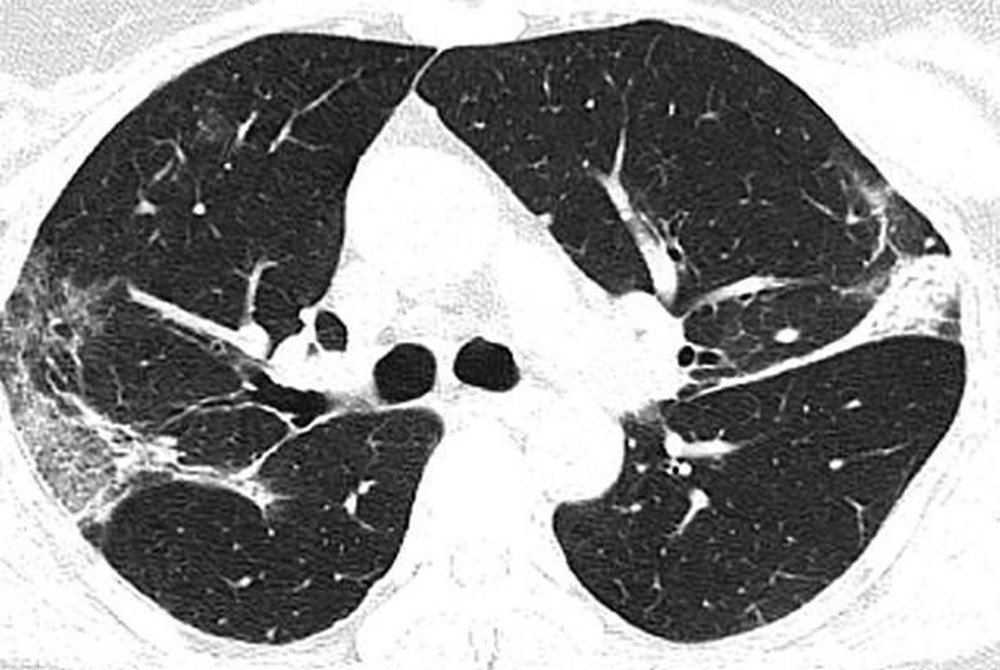

Wuhan'a seyahat ettikten sonra koronavirüse yakalanan 54 yaşında bir kadının bilgisayarlı tomografi taramaları da akciğerlerinde hava boşluklarının kısmen dolduğunu gösteriyor.